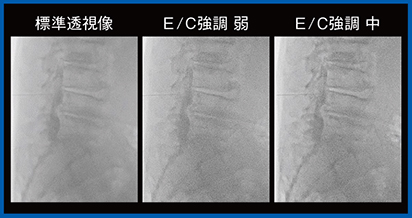

Accentは,画像のコントラストと鮮鋭性を増幅させデバイスや造影剤の視認性を確保する複合画像処理パラメータである。標準透視を含む5段階の強度があり,ダイヤル1つで透視を維持したまま手技に応じて最適な条件をリアルタイムに選択できる(図4)。そのため,単純に検査の種類などでモードを判断するのではなく,術者に確認しつつ,状況に応じたモードを選択,変更するのが望ましいと考える。

図4 新画像処理条件Accent の設定条件

厚さ5cmのアクリルファントム2枚の中間に,解像度チャート,ガイドワイヤ(0.035インチ)を挟んだ状態